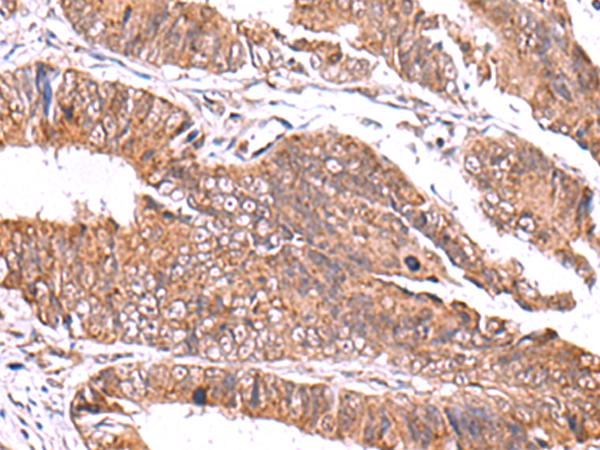

IHC positive control: |

Human colorectal cancer |

IHC Recommend dilution: |

50-300 |